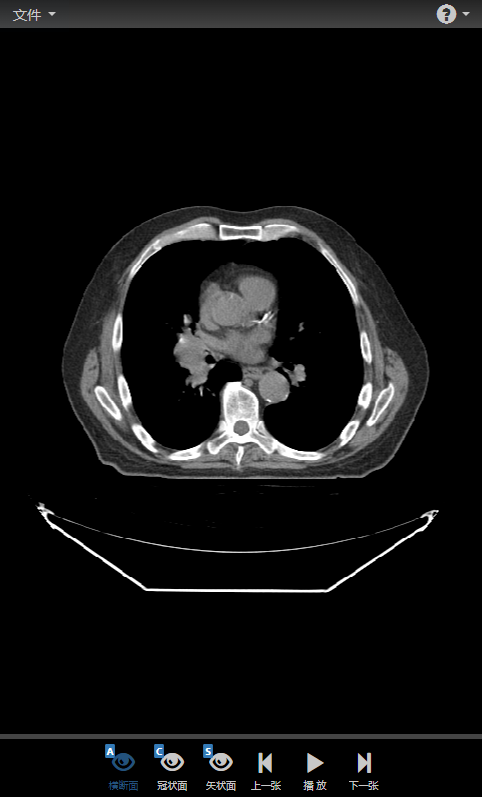

同时,DcmViewer支持移动端,当屏幕不足够大时,只显示最基本的视图布局切换和影像图片导航功能(样例数据将不支持冠状面和矢状面)。

小屏幕移动端: